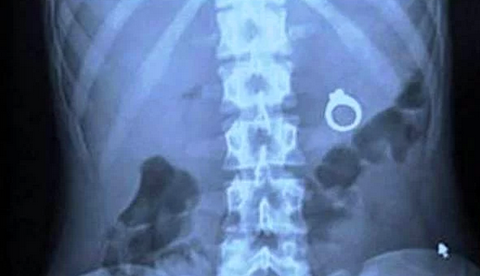

Amerikalı bir adam, sevgilisine sürpriz yapmak için aldığı tektaş

yüzüğü kızın milkshakeinin içine koyuyor.. Bu da sonucu